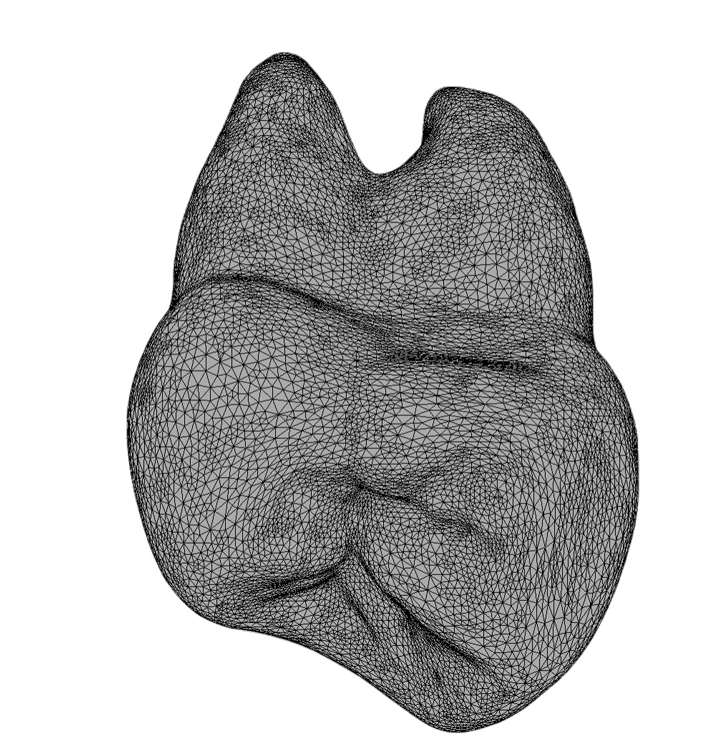

The canine fossa, a distinct anatomical feature, is the concavity on the mesial crown and root surface of the maxillary first premolar (Figure 1). This concavity extends from the crown into the root trunk, distinguishing it from the convex mesial crown surface of the second premolar. Larger and deeper than the incisive fossa, the canine fossa is separated by the vertical ridge of the canine eminence, which corresponds to the canine tooth socket.

(1.) A 3D image of the mesial aspect of a maxillary first premolar showing the canine fossa concavity extending from below the contact point onto the root surface.

Figure 1